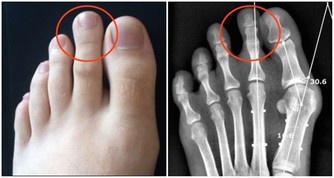

2、香菜:醫學研究表明,人過40歲後,骨生成減少,骨皮質變薄,尤以婦女為甚。此時,女性的骨頭猶如雞蛋,骨皮質薄似蛋殼,脆弱易碎。專家提醒,進入中年期的婦女應多吃含硼食物,以利身體吸收礦物質,保護骨骼,而香菜中的含硼量就很高。